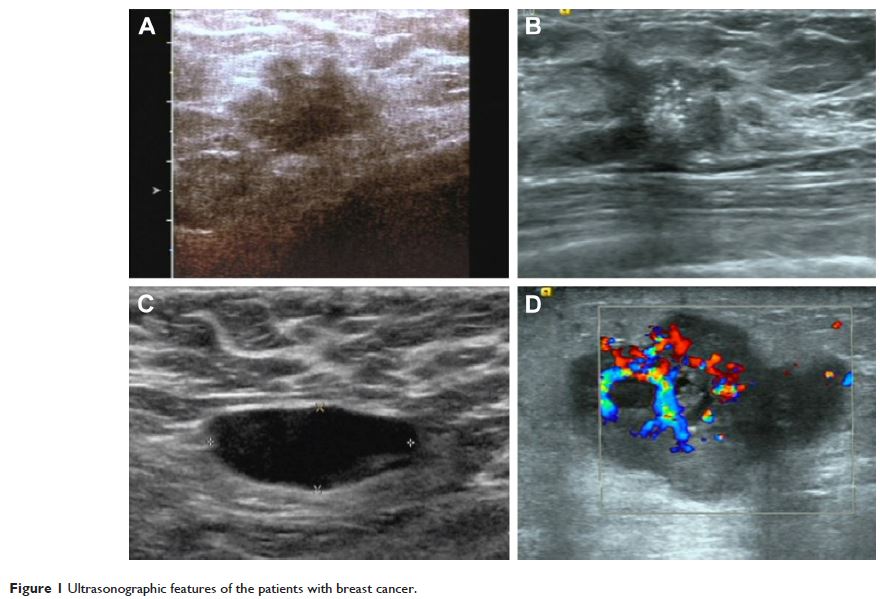

- 作者:唐琴,崔健毓,田中华,孙江川,王志刚,常淑芳,朱深银